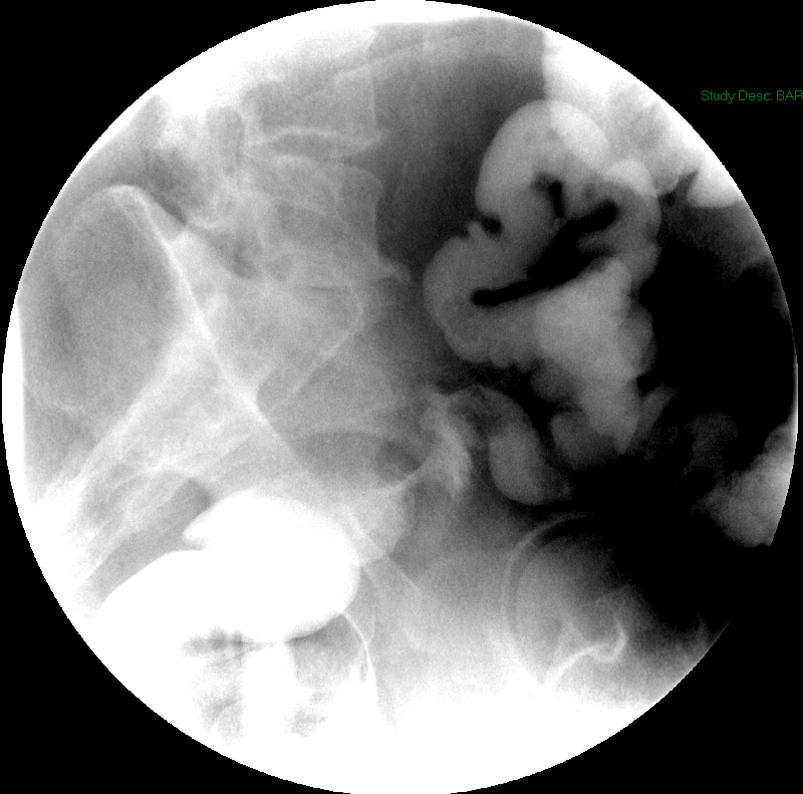

- Once the barium has reached the small bowel, you will go into the room and obtain spot images of the contrast material filled small bowel.

- Obtain images of the terminal ileum and the ileocecal valve filled with contrast material

(key image 6)

(key image 7)

(key image 8)

(key image 9)

(key image 10).

- Obtain spot images of the remainder of the small bowel

(key image 11)

(key image 12)

(key image 13)

(key image 14).

- Obtain images of all four quadrants. Use the compression paddle to separate loops of small bowel from each other.

- Evaluate for tethering of small bowel to any other structures.